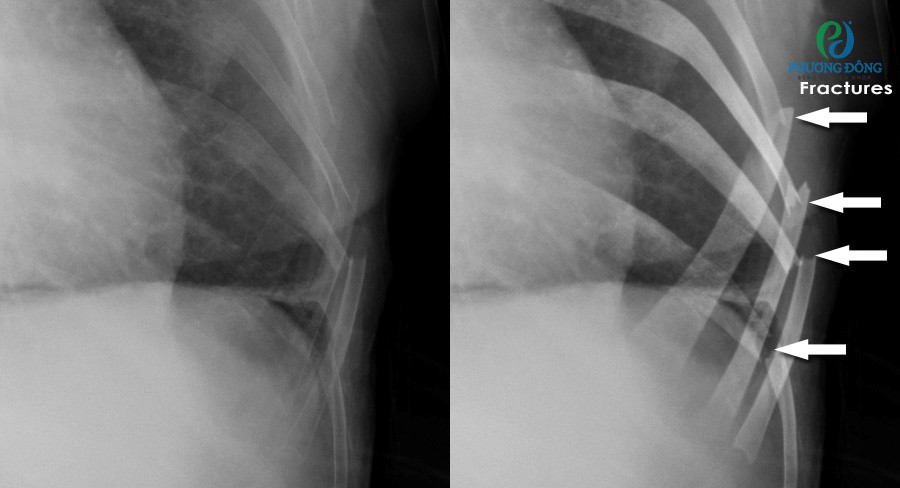

Tổn thương xương vùng ngực

X-quang phổi cũng hữu ích trong việc phát hiện gãy xương sườn, xương đòn và các bất thường ở cột sống ngực. Nhờ đó, bác sĩ có thể đánh giá mức độ tổn thương và đưa ra hướng xử trí phù hợp sau chấn thương hoặc trong quá trình theo dõi bệnh lý xương.

X-quang phổi cũng hữu ích trong việc phát hiện gãy xươngX-quang phổi cũng hữu ích trong việc phát hiện gãy xương